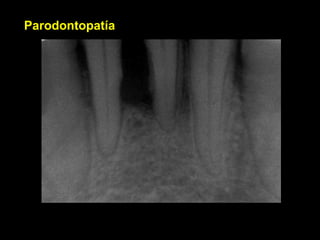

Parodontopatía

Encia sana

Inserción Gingivodentaria sana

Ruptura del anillo de

Kolhiker

Primer absceso gingivodentario sin compromiso

Oseo aparente.

Qué es

Profundización relativamente asintomática de la

Placa bacteriana

Absceso parodontal severo, con sintomatología franca

Destrucción del parodonto

Otro caso severo